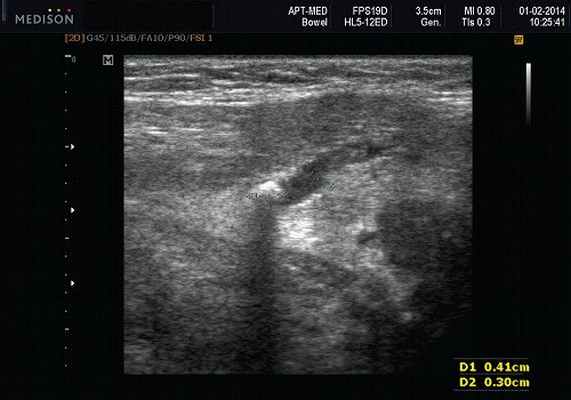

- обструктивные сиаладениты, развивающиеся при затруднении оттока слюны при обструкции выводного протока камнем (рис. 5-7) или сгустившимся секретом, а также вследствие рубцового стеноза протока. По распространенности процесса различают очаговый, диффузный сиаладениты и сиалодохит - воспаление выводного протока. Течение процесса может быть острым и хроническим;

Рис. 5. Камень протока поднижнечелюстной слюнной железы.

Рис. 6. Камень в паренхиме поднижнечелюстной слюнной железы.

Рис. 7. Камень в протоке поднижнечелюстной слюнной железы.